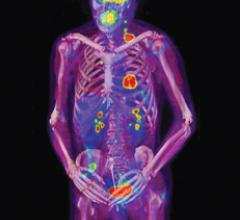

Single photon emission computed tomography (SPECT) remains a well-entrenched imaging modality for nuclear myocardial perfusion imaging (MPI) more than 30 years after its introduction. Due to SPECT’s reliability, cost-effectiveness and the wealth of data showing its clinical validation, it remains more common in MPI than its competition, positron emission tomography (PET).

Since it was named “Invention of the Year” by TIME magazine in 2000, positron emission tomography/computed tomography (PET/CT) has been hailed as a winning combination. It captures anatomical information from the CT and functional information from the PET to create a fused image at once, reducing some of the challenges that occur in fusing two images acquired at separate times from separate modalities.

Multimodality imaging in medicine can provide a physician with tools for making an accurate diagnosis prior to making treatment recommendations and helps the physician to lessen the potential for restaging, simplifying the image evaluation process and improving patient care in the future. The benefits also can be applied to the improvement of imaging in clinical trials, where precision and standardization is a necessity. For many diseases, including cancer, heart disease and certain brain disorders, the current and typical imaging process requires the acquisition of both positron emission tomography (PET) and computed tomography (CT) scans.